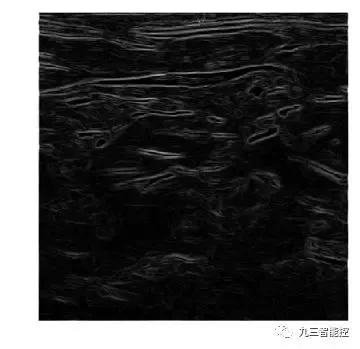

边缘检测(梯度模)

图像的梯度模的定义如下,它可以同时检测图像的水平和垂直方向的变化。